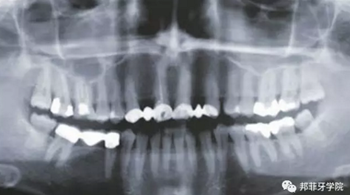

26歲女性患者,雙側(cè)上頜側(cè)切牙先天缺失,對原有修復(fù)體的“形態(tài)”、“光澤”等方面不滿意,希望重新修復(fù)(圖1&2)。12及22原為粘接橋修復(fù),11根管治療史;拆除原修復(fù)體后余鄰牙完整,未見病理性探診深度。無系統(tǒng)疾病史。患者期望值較高,告知治療流程佩戴臨時卡環(huán)義齒等(圖3)、費用、風(fēng)險后表示接受治療。

圖2:治療前全景片